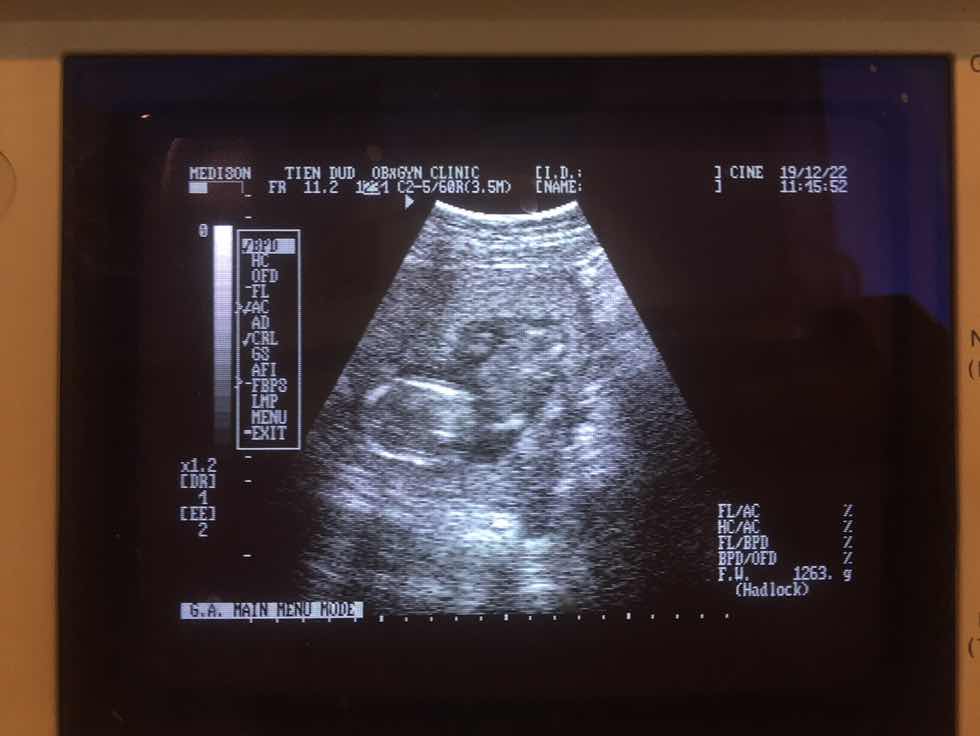

อยากรู้เพศลูกค่ะ รบกวนแม่ๆตอบให้ทีนะคะ

ขอถามแม่ๆหน่อยค่ะ ที่คุณหมอถ่ายให้คือระหว่างขาน้องใช่ไหมค่ะ แบบนี้ดูเพศออกไหมค่ะ พอดีเราอยากได้ลูกสาวอะค่ะ เราเป็นไข้หวัดใหญ่หนักรู้สึกว่าลูกไม่ดิ้นเลย เลยไปหาหมอค่ะ หมอเลยซาวให้ดูเพื่อความแน่ใจว่าลูกปกติแข็งแรงดี แต่ไม่กล้าถามหมอค่ะ เพราะตามจริงต้องเสียเงินเราฝากที่ ร.พ อื่น ที่จะถามแม่ๆ แบบนี้ดูเพศลูกออกไหมค่ะ แล้วเพศอะไรค่ะ ถ้าเพศหญิงแม่ๆซาวมาเป็นแบบไหนค่ะ ถ้าเพศชายแม่ๆซาวมาเป็นแบบไหนค่ะ ขอบคุณมากๆค่ะ ???